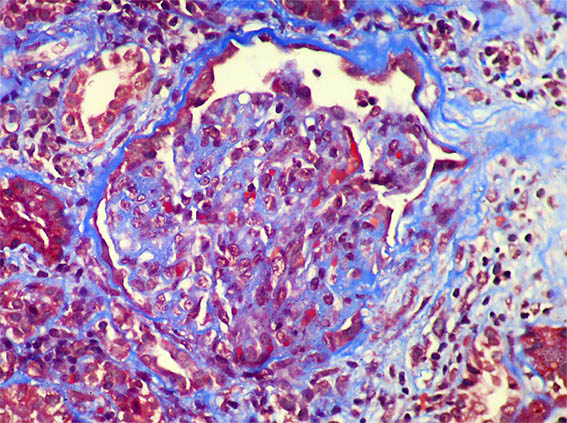

Figura 9. Tricrómico de Masson, X400. Una semiluna epitelial.